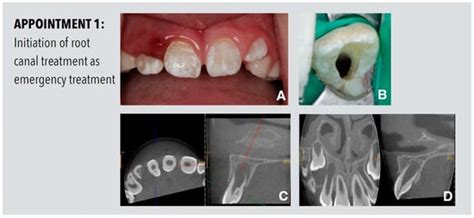

Root Maturation of an Immature Dens Invaginatus Despite Unsuccessful ...